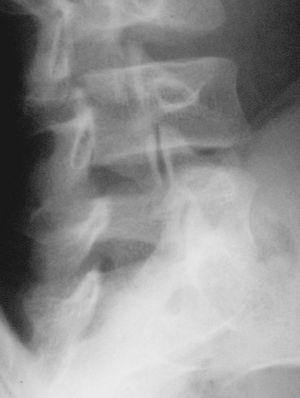

El nuevo estudio radiográfico demuestra espondilólisis L5 derecha y persistencia de integridad del hemiarco izquierdo (figs. 6 y 7). Igualmente, el estudio radiográfico dinámico demuestra establidad completa de la charnela lumbosacra (fig. 8). Por todo ello se planea el alta deportiva, aunque se le recomienda continuar un mes más el tratamiento, demorando el regreso a la práctica deportiva.

Figura 6

Figura 7